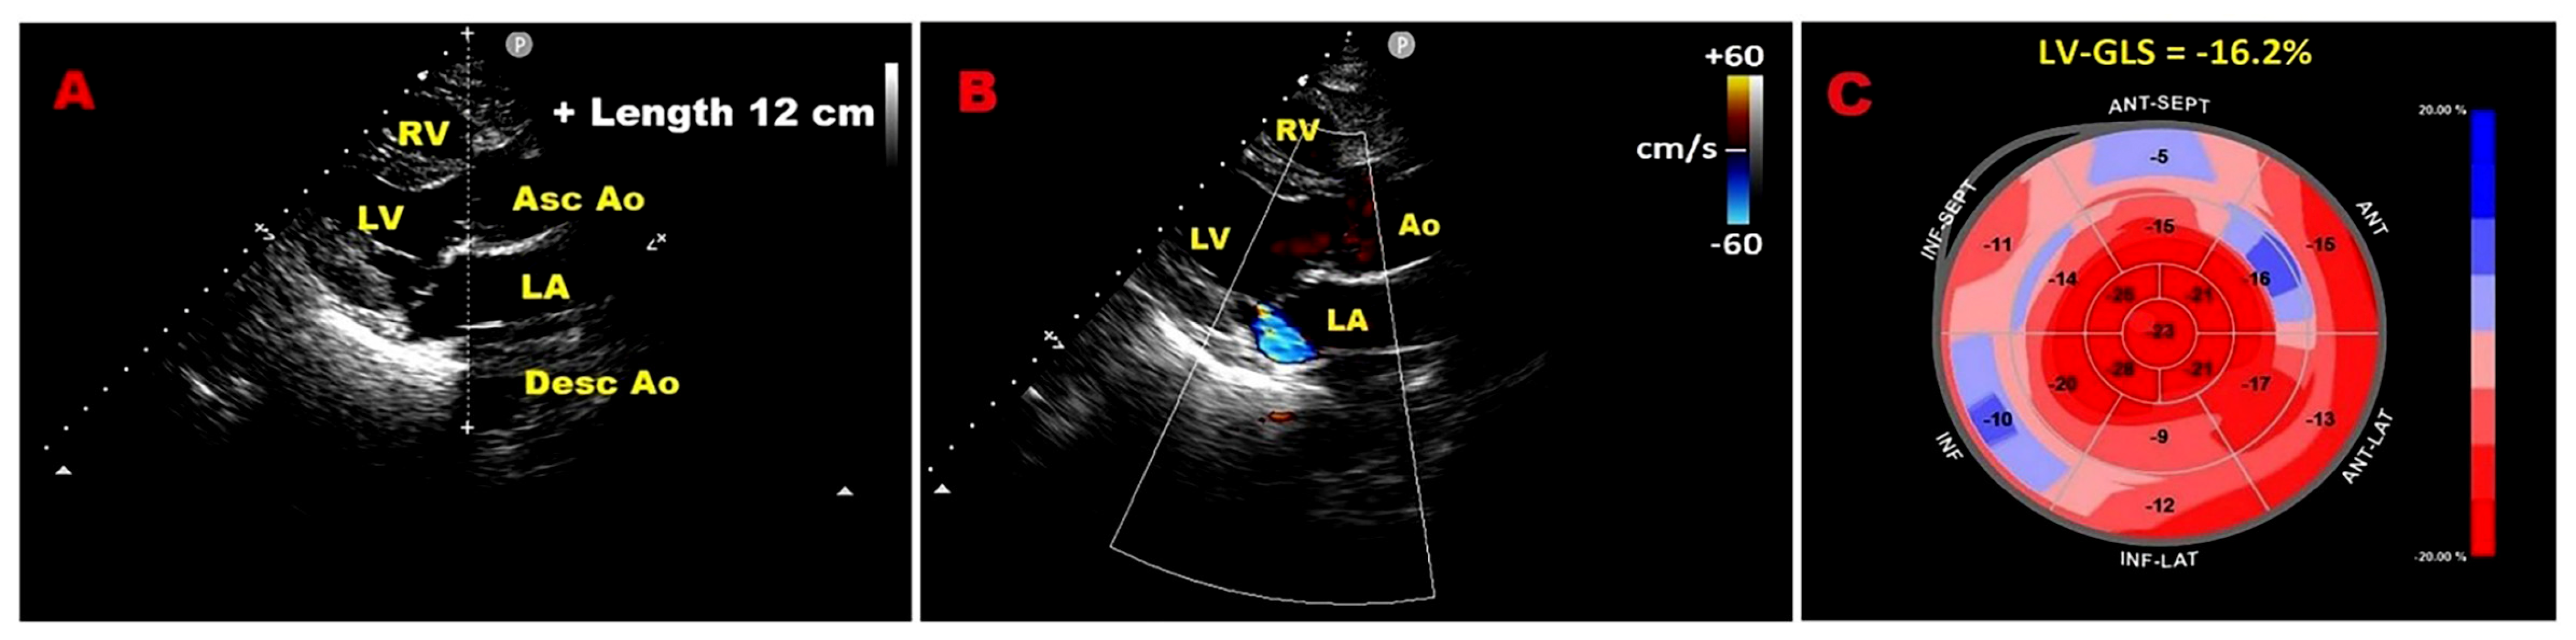

3.5. Left Atrial Size

3.6. Left Atrial Reservoir Strain

3.7. Pulmonary Hypertension